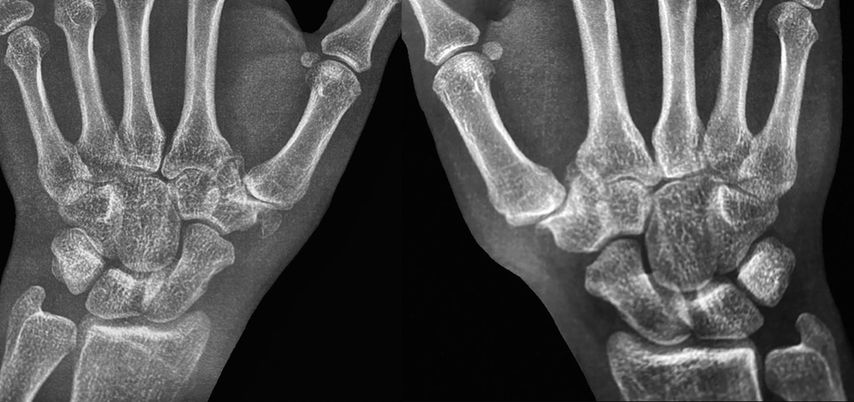

Zwischen 2009 und 2018 wurde dieses Verfahren an unserer Klinik bei 24 Patienten mit chronischer Instabilität des CMC1-Gelenkes angewendet. Eine Nachuntersuchung hinsichtlich klinischer Beschwerden und radiologischer Parameter war bei 12 Patienten (insgesamt 15 operierte Daumen; davon 3 links, 6 rechts, und 3 beidseitig) durchschnittlich 3,5 Jahre (1,3–5,8 Jahre) postoperativ möglich. Das durchschnittliche Alter bei Operation betrug 23,2 Jahre (7,4–41,3 Jahre). Alle Patienten waren mit dem postoperativen Ergebnis zufrieden und zeigten eine klinische Besserung hinsichtlich des DASH-Scores (durchschnittlich 13,3), des Schmerzes (VAS-Score in Ruhe durchschnittlich 1,1, bei Belastung 2,8) und des Nelson-Scores (durchschnittlich 87,7 im Vergleich zur nicht operierten Seite von 98,5). Eine funktionelle Besserung (Kapandji-Opposition durchschnittlich 9,8) und Zunahme der Greifkraft (durchschnittlich 24,6kg) wurden ebenfalls beobachtet. Nur eine Patientin berichtete von einem Rezidiv des Instabilitätsgefühls nach 3,5 Jahren postoperativ, jedoch ohne Notwendigkeit einer Revisionsoperation. Radiologisch wurde in 5 Fällen eine Hypoplasie des Os trapezium mit vermehrter mittel- bis hochgradiger Translation des ersten Metacarpale nach radial beobachtet. Fälle ohne Hypoplasie zeigten eine leichte bis mittlere Translation in radiologischen Stressaufnahmen.19

An unserer Klinik hat sich ebenfalls die Verwendung eines APL-Sehnenstreifens zur Stabilisierung des CMC1-Gelenkes etabliert. Hierfür wird ein longitudinaler Hautschnitt von etwa 5–6cm dorsoradial über dem CMC1-Gelenk durchgeführt, anschließend die APL-Sehne freipräpariert und ein Sehnenstreifen am Ansatz von proximal nach distal gelöst. Im Gegensatz zu Langers Verfahren wird kein intraossärer Kanal zur Rekonstruktion verwendet, sondern es werden stumpf zwei transverse Weichteilkanäle geschaffen. Diese sollten in der Tiefe unterhalb der Kapsel und der Ligamente liegen und es ist auf einen Abstand von 12–15mm zu achten. Der APL-Sehnenstreifen wird nun durch die transversen Weichteilkanäle in der Form einer 8er-Schlinge durchgezogen und mit FiberWire (Arthrex Inc., Naples, Florida) mit mehreren Knoten in sich vernäht (siehe Abb. 4). Im nächsten Schritt erfolgt die passive Stabilitätsprüfung. Das postoperative Prozedere besteht aus einer Daumenschiene in Abduktion für 6 Wochen und Ergotherapie. Eine sportliche Aktivität ist nach 12 Wochen gestattet.